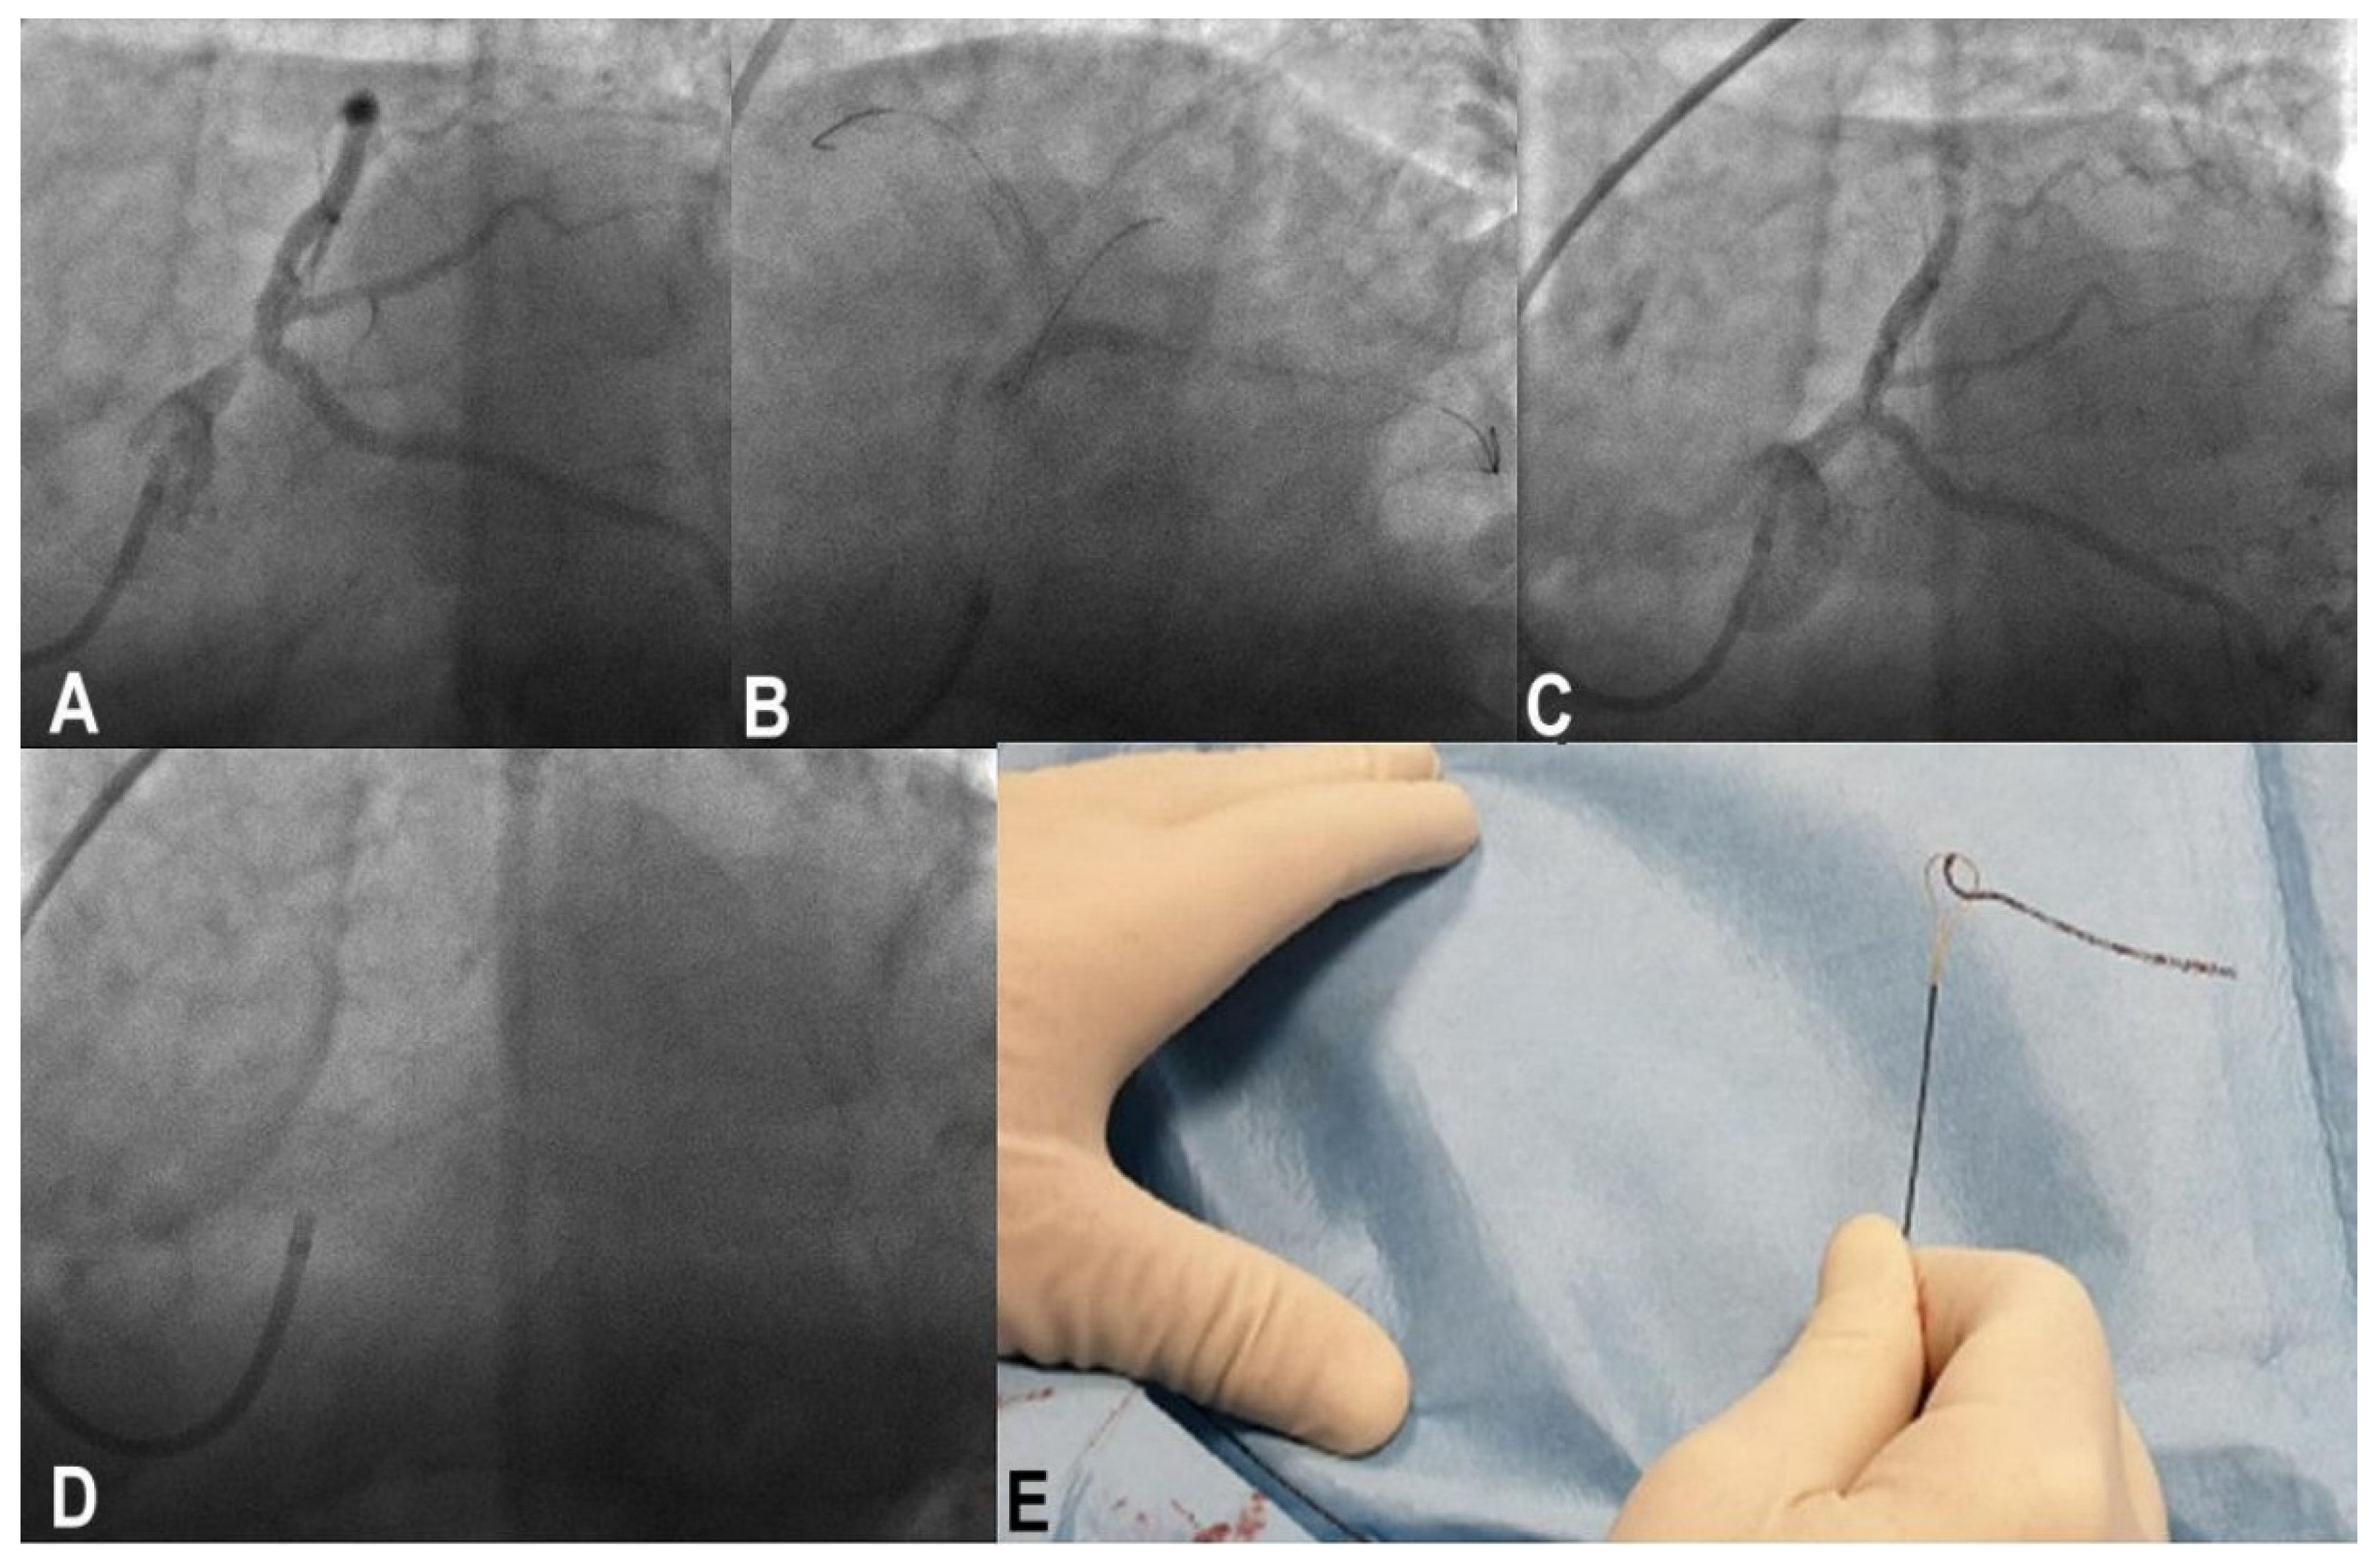

3.7. Wire Entrapment and Fracture